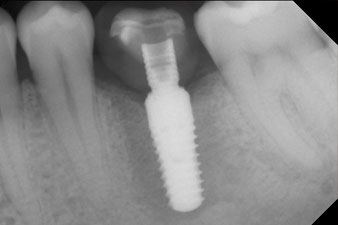

measuring probe

Fig. 6: Ten weeks later the gingiva former, which was screwed in place after placement of the implant, can be removed. In the linguo-buccal direction the ISQ value was virtually unchanged at 63 (measuring probe in proximity at a distance of 2-3 mm).

These values could have indicated open healing or even immediate restoration. Due to the insufficient crestal bone volume at the implant, the region was augmented with the bone chips collected during preparation of the implant bed and sutured to exclude saliva.

The implant was uncovered two months later and a gingiva former was screwed in (no picture).